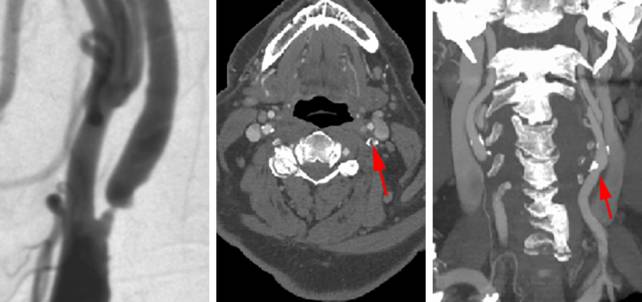

颈动脉狭窄患者需要完整的医疗评估。必须完成颈动脉血管结构相关的影像学检查,尽管超声对于定期评估和随访监测而言是合理的做法,但通常而言用于手术计划略显不足。笔者也发现MRA有高估狭窄程度的趋势。因此,笔者更愿意选择头颈部CTA或者DSA。颈内动脉颅内段存在串联病变的患者应该被排除在外,因为这些特殊的病例仅用CEA治疗不太可能获益。

图1. 一例左侧溃疡性、部分钙化的斑块导致颈动脉高度狭窄,术前血管造影(左图)和CTA(右二图箭头)证实。